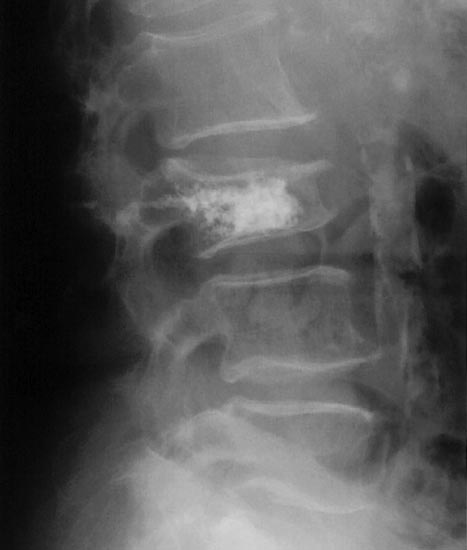

Background: Osteoporosis is an age-related skeletal condition of bone, with increasing prevalence in older populations. Insufficiency of the bone is associated with increased disability and mortality. Vertebral fractures are commonly secondary to osteoporosis, however only a proportion of patients may present clinically with identifiable symptoms. Percutaneous vertebroplasty is an interventional method of managing such patients.

Results: Vertebroplasty reduces pain in the short-term (up to 2 weeks) after surgery and has sustained effects in improving quality of life. The long-term effects are difficult to establish due to the underlying osteoporosis disease progression and comorbidities.

Conclusion: Vertebroplasty is worthwhile in treating acute vertebral fractures associated with pain. However more research is needed to fully determine its effectiveness in the long term.

Radiological Society of North America. Osteoporosis. Available at <http://www.radiologyinfo.org/en/photocat/gallery3.cfm?image=xray-osteoporosis-vertebroplasty.jpg&pg=osteoporosis > Accessed 13 December 2014.